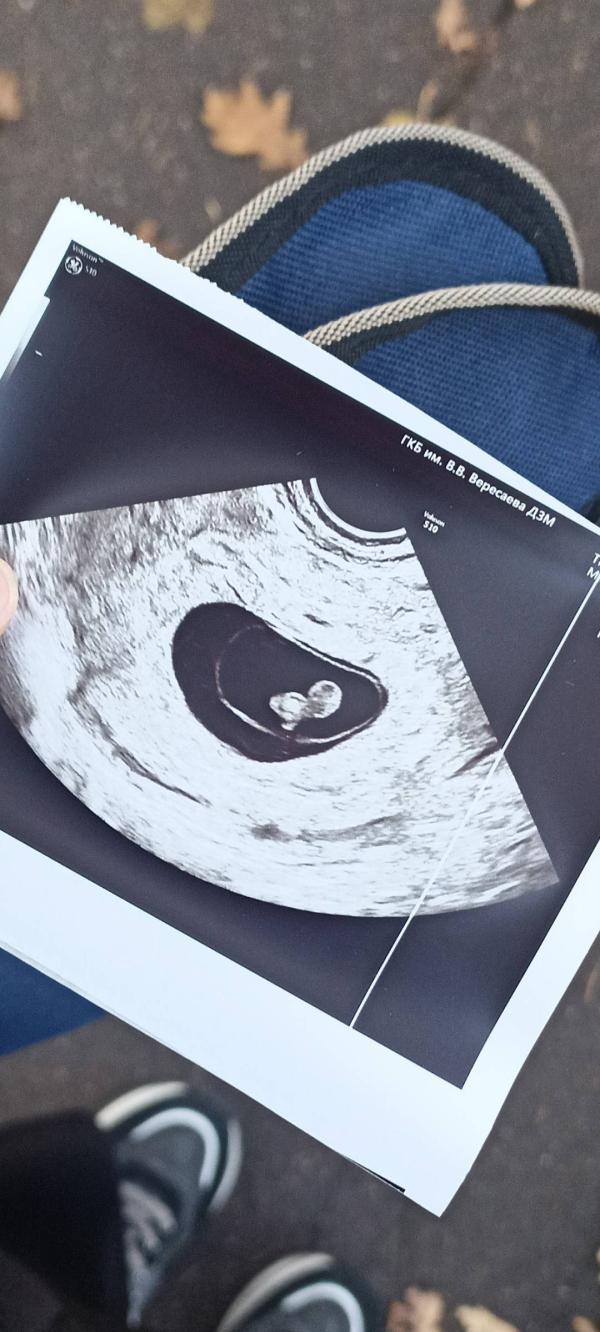

Мой маленький ангелочек, сегодня узнала что, он уже покинул нас неделю назад😭

15 октябрь последний раз услышала сердечко😭

До сих пор слышу голос УЗИстки😭